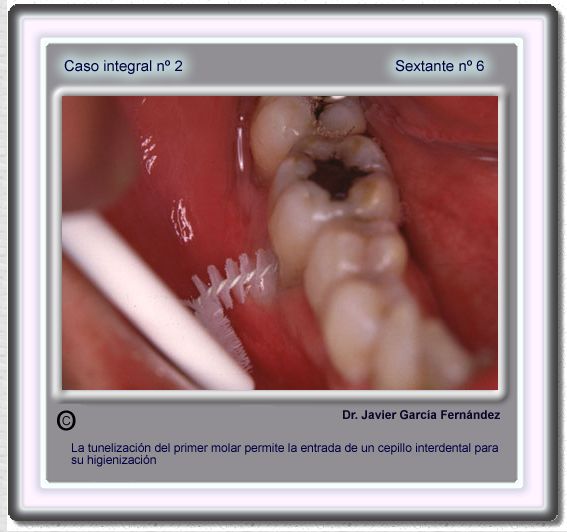

image 88